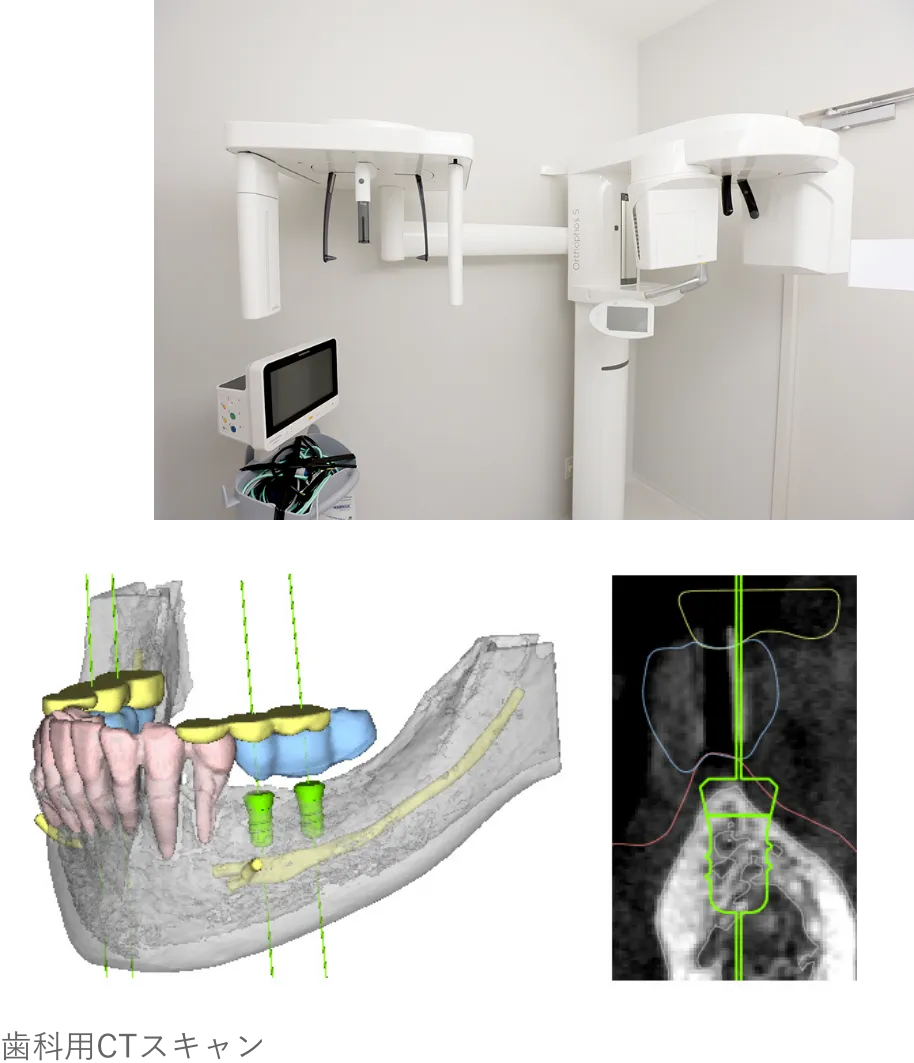

MEDICAL EQUIPMENT

CTスキャンを活用し、

患者様の口腔内を

3Dデータで精密に解析

加藤総合歯科・矯正歯科では、CTスキャンにより口腔内を3D化し、

コンピューターシステム「ビオナ」で歯の状態を詳しく解析します。

専門医とコンピュータ技術が連携し、インプラントの位置や角度をミリ単位で正確に決定、手術時のリスクを最小限に抑えます。

精密な手術計画と

シミュレーションを通じて、

治療の負担を最小限に抑えます。

CTスキャンを活用して口腔内の立体的なモデルを作成し、歯の状態を正確に分析。その結果を基に精密なインプラント治療計画を立てます。

インプラント手術前に精密な検査を行い、従来の歯科用レントゲンだけでなく、CTスキャンで骨の状態や神経の走行を把握し、さらにお口の型取りで歯肉の状態も調べます。これにより、治療計画をコンピューター上でシミュレーションし、安全性を確保した治療を行っていますので、安心してお任せください。

CTスキャンを使用して精密なシミュレーションを行い、骨の状態や上顎洞の位置を正確に確認していますので、このようなトラブルは発生しません。

CTスキャンを使用せずレントゲンだけでインプラント手術を進めると、骨を傷つけてしまうリスクがあります。特に上顎では、上顎洞に穴を開けて炎症を引き起こす可能性もあります。

当院の対策法

CTスキャンを使用して精密なシミュレーションを行い、骨の状態や上顎洞の位置を正確に確認していますので、このようなトラブルは発生しません。